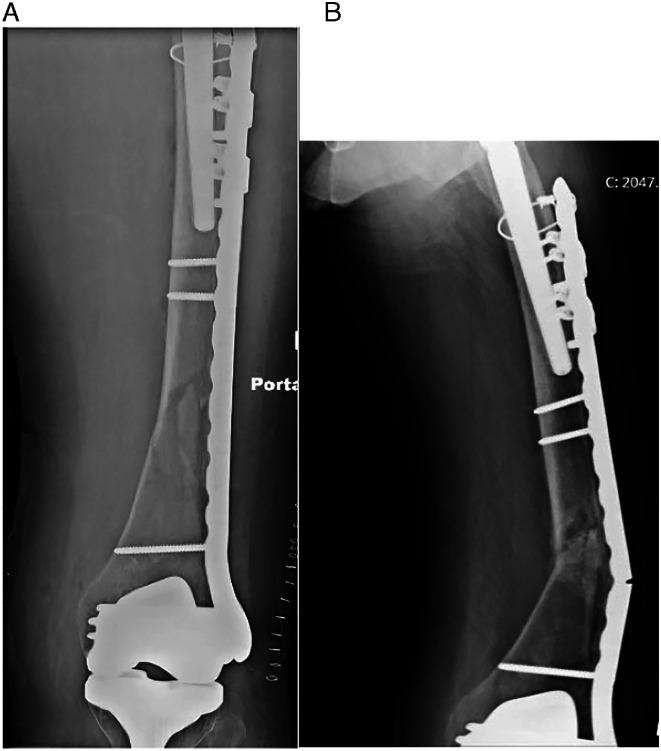

The locking attachment plate (LAP) can be added to a locking compression plate (LCP) to allow the fixation of locking screws bicortically around a femoral implant. We aimed to examine surgical and fracture characteristics associated with healing for periprosthetic femur fractures (PPFFx) treated with constructs employing LAP fixation. We hypothesize that the addition of an LAP provides stable peri-implant fixation.

MATERIALS &METHODS: We retrospectively reviewed a consecutive series of 28 PPFFx surgically treated with LCP-LAP constructs by 4 surgeons from 2015-2020. Fractures were classified and grouped using the Vancouver Classification System and included 12 B1, 2 B2, 11 C fractures, and 3 fractures around other stemmed implants. Primary outcome measures included hardware failure such as screw pullout, broken screws, and plate fracture. Clinical complications including infection, non-union, malunion, and reoperation were recorded.

No LAP failures, screw pullout, or broken screws were observed. Two fractured plates (7.1%) occurred in patients with Vancouver C fracture types. Overall complication rate was 17.9% and included 3 non-unions, 1 deep infection, and 1 implant loosening with painful hardware, each requiring reoperation. Differences were observed between unions and nonunions for total number of screws (12.4 vs 14.7, = .005) and number of locking screws used (8.04 vs 11.3, = .03).

The LAP provides adequate fixation and low failure rates where fixation is required around a well-fixed stem. When failures occur, it is from plate breakage and not due to failure of fixation at the area of plate-stem overlap.